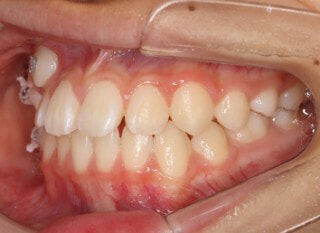

小児期第二段階

開始時

小児期の第二段階

治療中